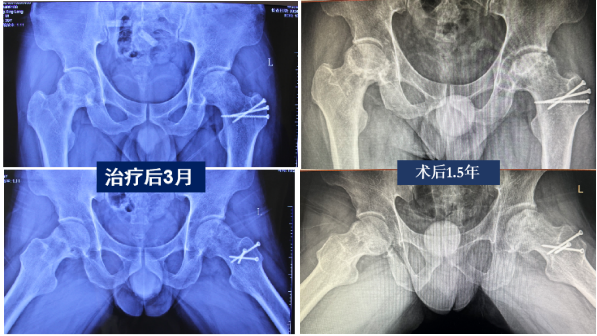

术前X片可见双侧股骨头均为JIC C1型,外侧壁部分保留,坏死病灶见片状透亮影,予行髓芯减压植骨术

术后随访可见坏死病灶片状硬化,修复良好,外侧壁增厚,股骨头形态保持良好